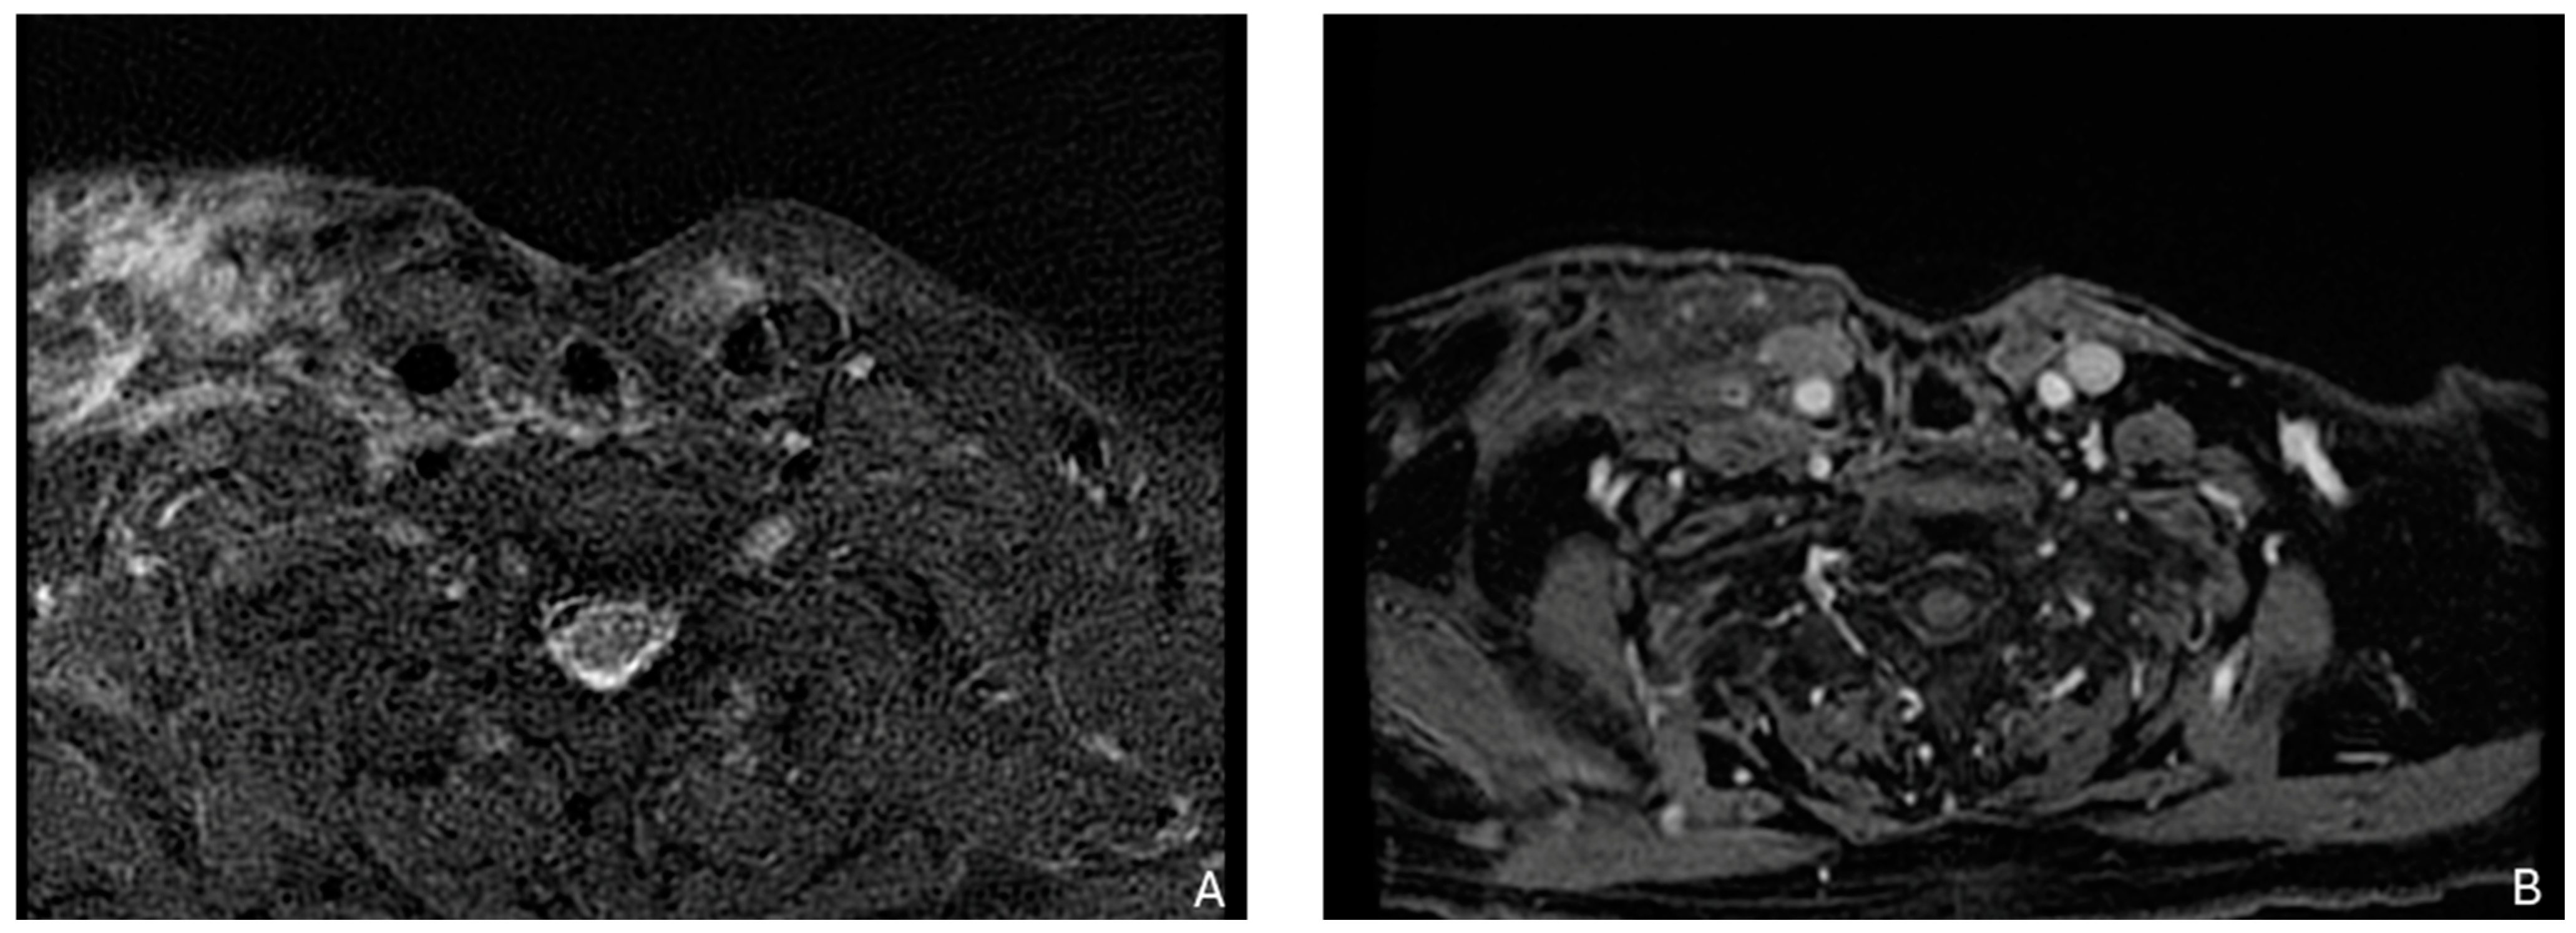

- Kim, S.Y.; Beer, M.; Tshering Vogel, D.W. Imaging in Head and Neck Cancers: Update for Non-Radiologist. Oral. Oncol. 2021, 120, 105434. [Google Scholar] [CrossRef] [PubMed]